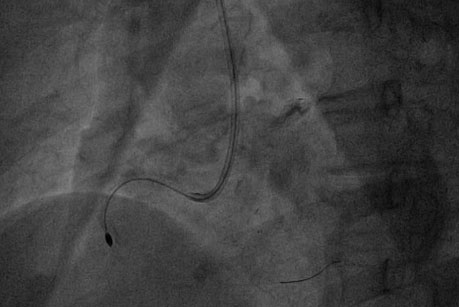

患者为老年女性,冠脉造影显示:右冠状动脉严重狭窄,伴有极为严重的钙化,需要行冠状动脉旋磨术治疗。但该患者血管发育极为粗大,直径在4mm以上,需要超大直径的旋磨头。目前国内常用的旋磨头直径为1.25-1.75mm, 配备2.0mm及以上旋磨头的医院很少。研究显示,我国女性仅有40%可以耐受7F鞘管(2.85mm),很少能容纳8F的鞘管(直径3.22mm)。但该患者需要超大直径旋磨头治疗,因此也需要大直径的8F指引导管和鞘管输送。

经过冠脉介入团队充分讨论后,制定了个体化的介入治疗方案,择期为患者进行冠状动脉旋磨术。心内科执行主任赵慧强将友谊医院通州院区备好的2.0mm和2.15mm旋磨头调至我院,亲自为患者进行介入治疗。他采用了自己首创的球囊辅助(BAT)的无鞘技术,经桡动脉成功将8F导管送至冠脉开口,先后使用2.0mm和2.15mm旋磨头进行旋磨,最终成功植入2枚支架,手术顺利完成,效果非常满意。患者目前已康复出院。